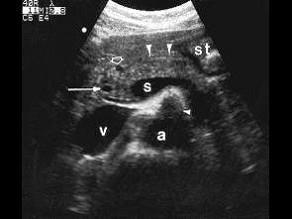

男,27岁,健康体检,超声图中箭头所指为?(?)A.肠系膜上动脉B.肠系膜上静脉C.胆总管D.肝动脉E.门静脉

问题 男,27岁,健康体检,超声图中箭头所指为?(?)

选项 A.肠系膜上动脉 B.肠系膜上静脉 C.胆总管 D.肝动脉 E.门静脉

答案 C